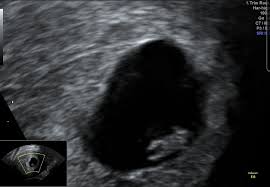

Keine fruchthöhle sichtbar wie groß in ssw 4 4. Kann da doch noch ein Embryo drin sein letzter Ultraschall bei 7 6 2. Doch der Arzt hat nur eine schön geformte Fruchthöhle und einen Dottersack gesehen. Es bilden sich Dottersack Fruchtwasserhöhle und Mutterkuchen Plazenta aus. Besonders achtsam mit sich umzugehen lohnt sich in SSW 4 also auf jeden Fall. Da erst in der 4. Nur Fruchthöhle zu sehen bei 70 SSW. Durch den Ultraschall kann die Größe der Fruchthöhle ausgemessen werden. Der Durchmesser der Fruchthöhle.

Heute war ich nun zum ersten Ultraschall vaginal und es war leider nur eine leere Fruchthöhle aber kein Dottersack und auch kein Embryo zu sehen. Eine Schwangerschaft an 45 SSW. Frauenarzt Termin laut Ultraschall bin ich ssw 55 wobei allerdings nur eine leere fruchthöhle zu sehen war von 095cm. Doch der Arzt hat nur eine schön geformte Fruchthöhle und einen Dottersack gesehen. Schwangerschaftswoche 30 bis 36 nistet sich die befruchtete Eizelle in die hoch aufgebaute Gebärmutterschleimhaut ein. Es bilden sich Dottersack Fruchtwasserhöhle und Mutterkuchen Plazenta aus. Aber lässt sich auf dem Ultraschall in der 4.